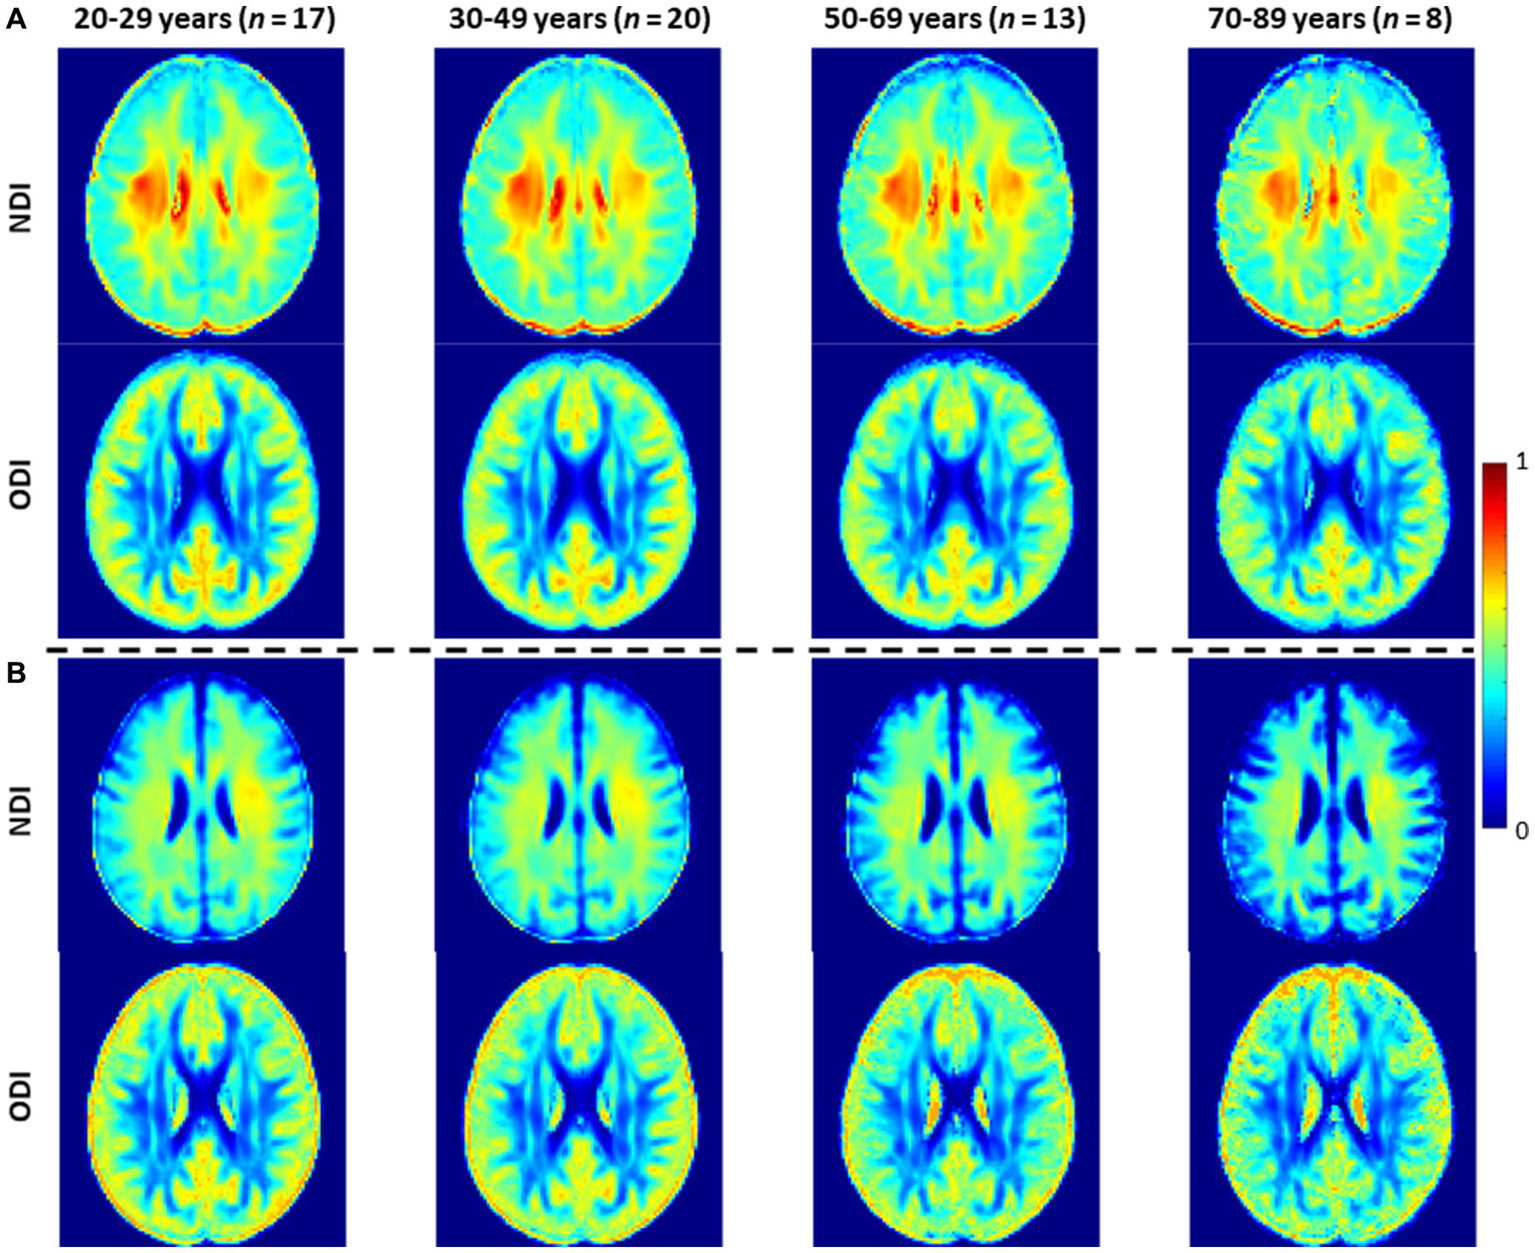

Figure 3 shows representative average NDI and ODI maps for different age intervals corresponding to young, middle, late middle and late adulthood. Visual inspection indicates increases in NDI values from early adulthood through middle age (i.e., 40–59 years), followed by lower NDI values in several brain regions, consistent with progressive increases in axonal density followed by reductions at older ages. Furthermore, we note that different regions exhibit different patterns in the association of NDI with age. In contrast, the ODI maps exhibit low regional variations with age. Remarkably, NDI maps derived from NODDI exhibit values that exceed 0.7 (i.e., 70%) in several cerebral WM structures, while the NDI values derived using C-NODDI are considerably lower. Moreover, ODI maps derived using NODDI and C-NODDI were virtually identical. Indeed, our quantitative comparison, presented in Figure 4, indicates weak to moderate regional Pearson correlation between the NDI values derived using NODDI and those derived using C-NODDI for all ROIs investigated, in agreement with visual inspection (Figure 3). In contrast, strong regional correlations were observed between the ODI values derived from the two NODDI approaches.

Figure 3

NDI and ODI maps represented as averaged participant maps calculated over four age intervals. Results are shown for a representative slice. NDI and ODI maps derived (A) using the original NODDI approach, and (B) using the C-NODDI approach. While the ODI values derived using both approaches are virtually identical, C-NODDI provides substantially lower NDI values than those derived using NODDI.